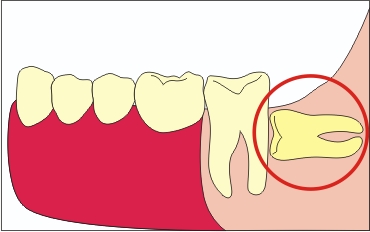

A mediális dőlése a Nyolcak Csoportja

Ez a rendelkezés tilt provokálja a fogszuvasodás kialakulásának, mint magától bölcsességfog, és a fogat állt mellette. Ha a lejtő erős, akkor a gyökér a hetedik foga is oldódni kezdenek, ami az ő eltávolítását. Ezen túlmenően, a csírázó az ilyen szögben, a fogat is elmozdulhatnak az egész sorozat, ami azt eredményezi, annak deformációját.

Ebben az esetben a személy léphet nemcsak fájdalom helyén fog kitörés, hanem fejfájás, zsibbadás az arc vagy az ajkak. Ez okozta kompresszió a mandibula ideg. Egy ilyen kiviteli alaknál, a nehéz fogat lehet elhelyezve teljesen vízszintesen.